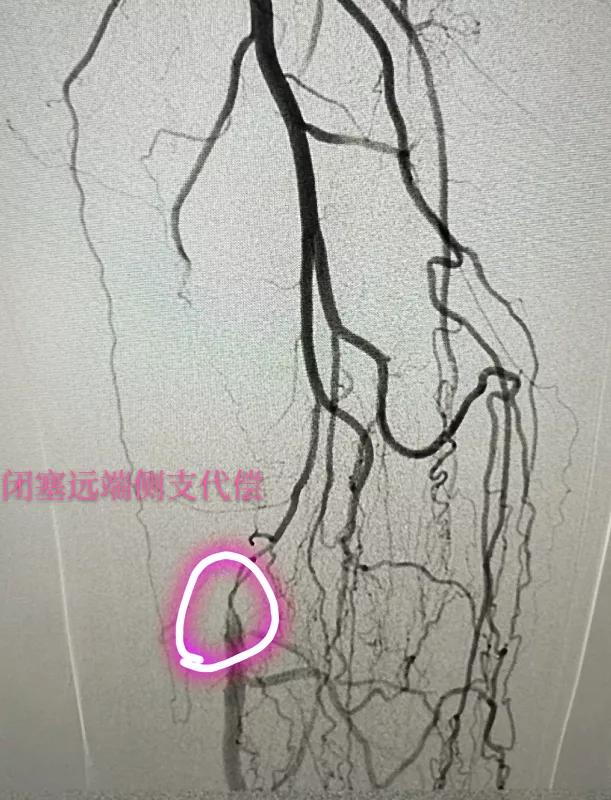

患者入院治疗并经下肢动脉CTA检查诊断,其腹主动脉粥样硬化,左侧髂总动脉、左侧髂内外动脉、右侧髂内动脉管腔狭窄,左侧股浅动脉近中段闭塞并周围侧枝循环形成;左侧腘动脉远端轻度狭窄;左侧胫前动脉近端重度狭窄,中远段闭塞;左侧胫后动脉近段多发狭窄。

术前造影检查

血管外科主任程勇、副主任赵平带领团队在介入导管室为患者实施局麻下左下肢动脉造影+球囊扩张成形+支架植入术,成功为患者实施了下肢动脉硬化闭塞症微创治疗。

术后造影显示支架内血流通畅,狭窄消失,患者安返病房。术后第二天,唐大叔就下地行走,胫后动脉搏动良好,左下肢肌力及肌张力正常。